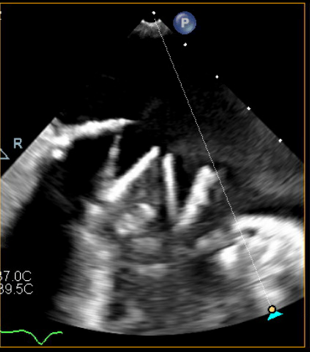

We performed transseptal puncture using Versacross wire (Baylis Medical) and Baylis catheter, followed by septostomy using a 14 mm Armada balloon (Abbott) (Figure 3). We then advanced the AlphaVac system (Angiodynamics) to the left atrial and directed the tip of the funnel towards the thrombus (Figure 4), which was successfully removed after multiple runs of aspiration using the AlphaVac system. (Figure 5A, B). The system was then removed, and the femoral venous access was closed using Perclose (Abbott). The patient was transferred to the cardiothoracic intensive care unit for further monitoring. Unfortunately, after transfer, a stroke occurred in the patient’s right middle cerebral artery. Her goals of care were discussed with the family, and she was transitioned to comfort care. She died 3 days post-procedure.